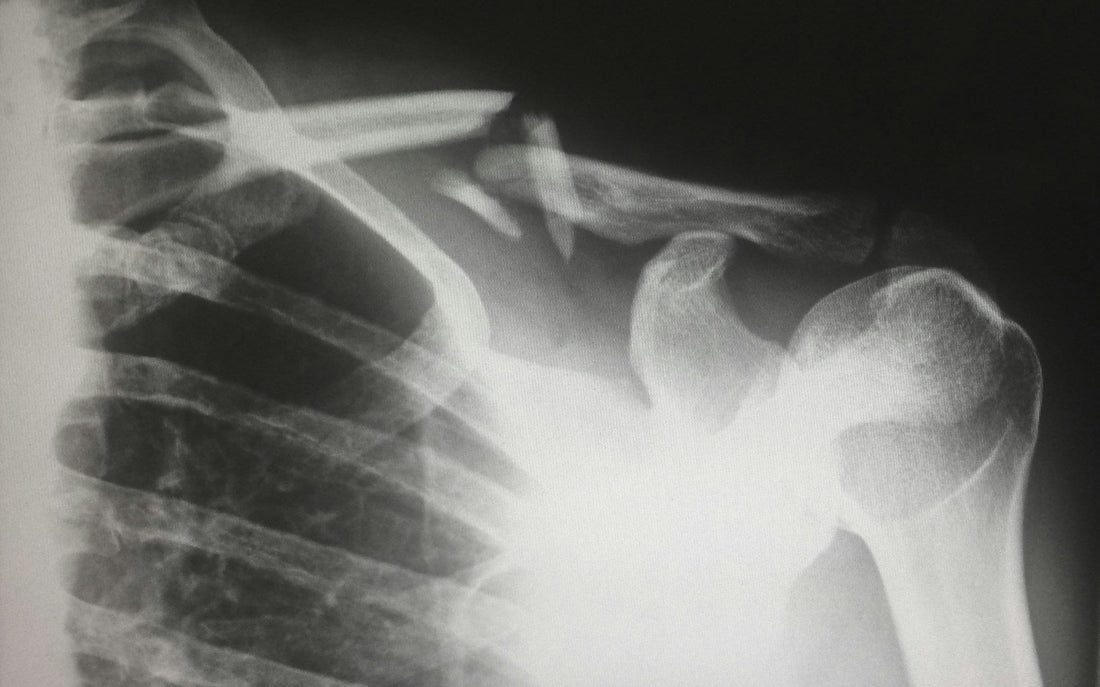

Accelerates Fracture Healing

Another study examined shilajit’s role in fracture healing. The trial revealed that shilajit reduced tibia fracture recovery time, with patients experiencing faster healing than those on a placebo.